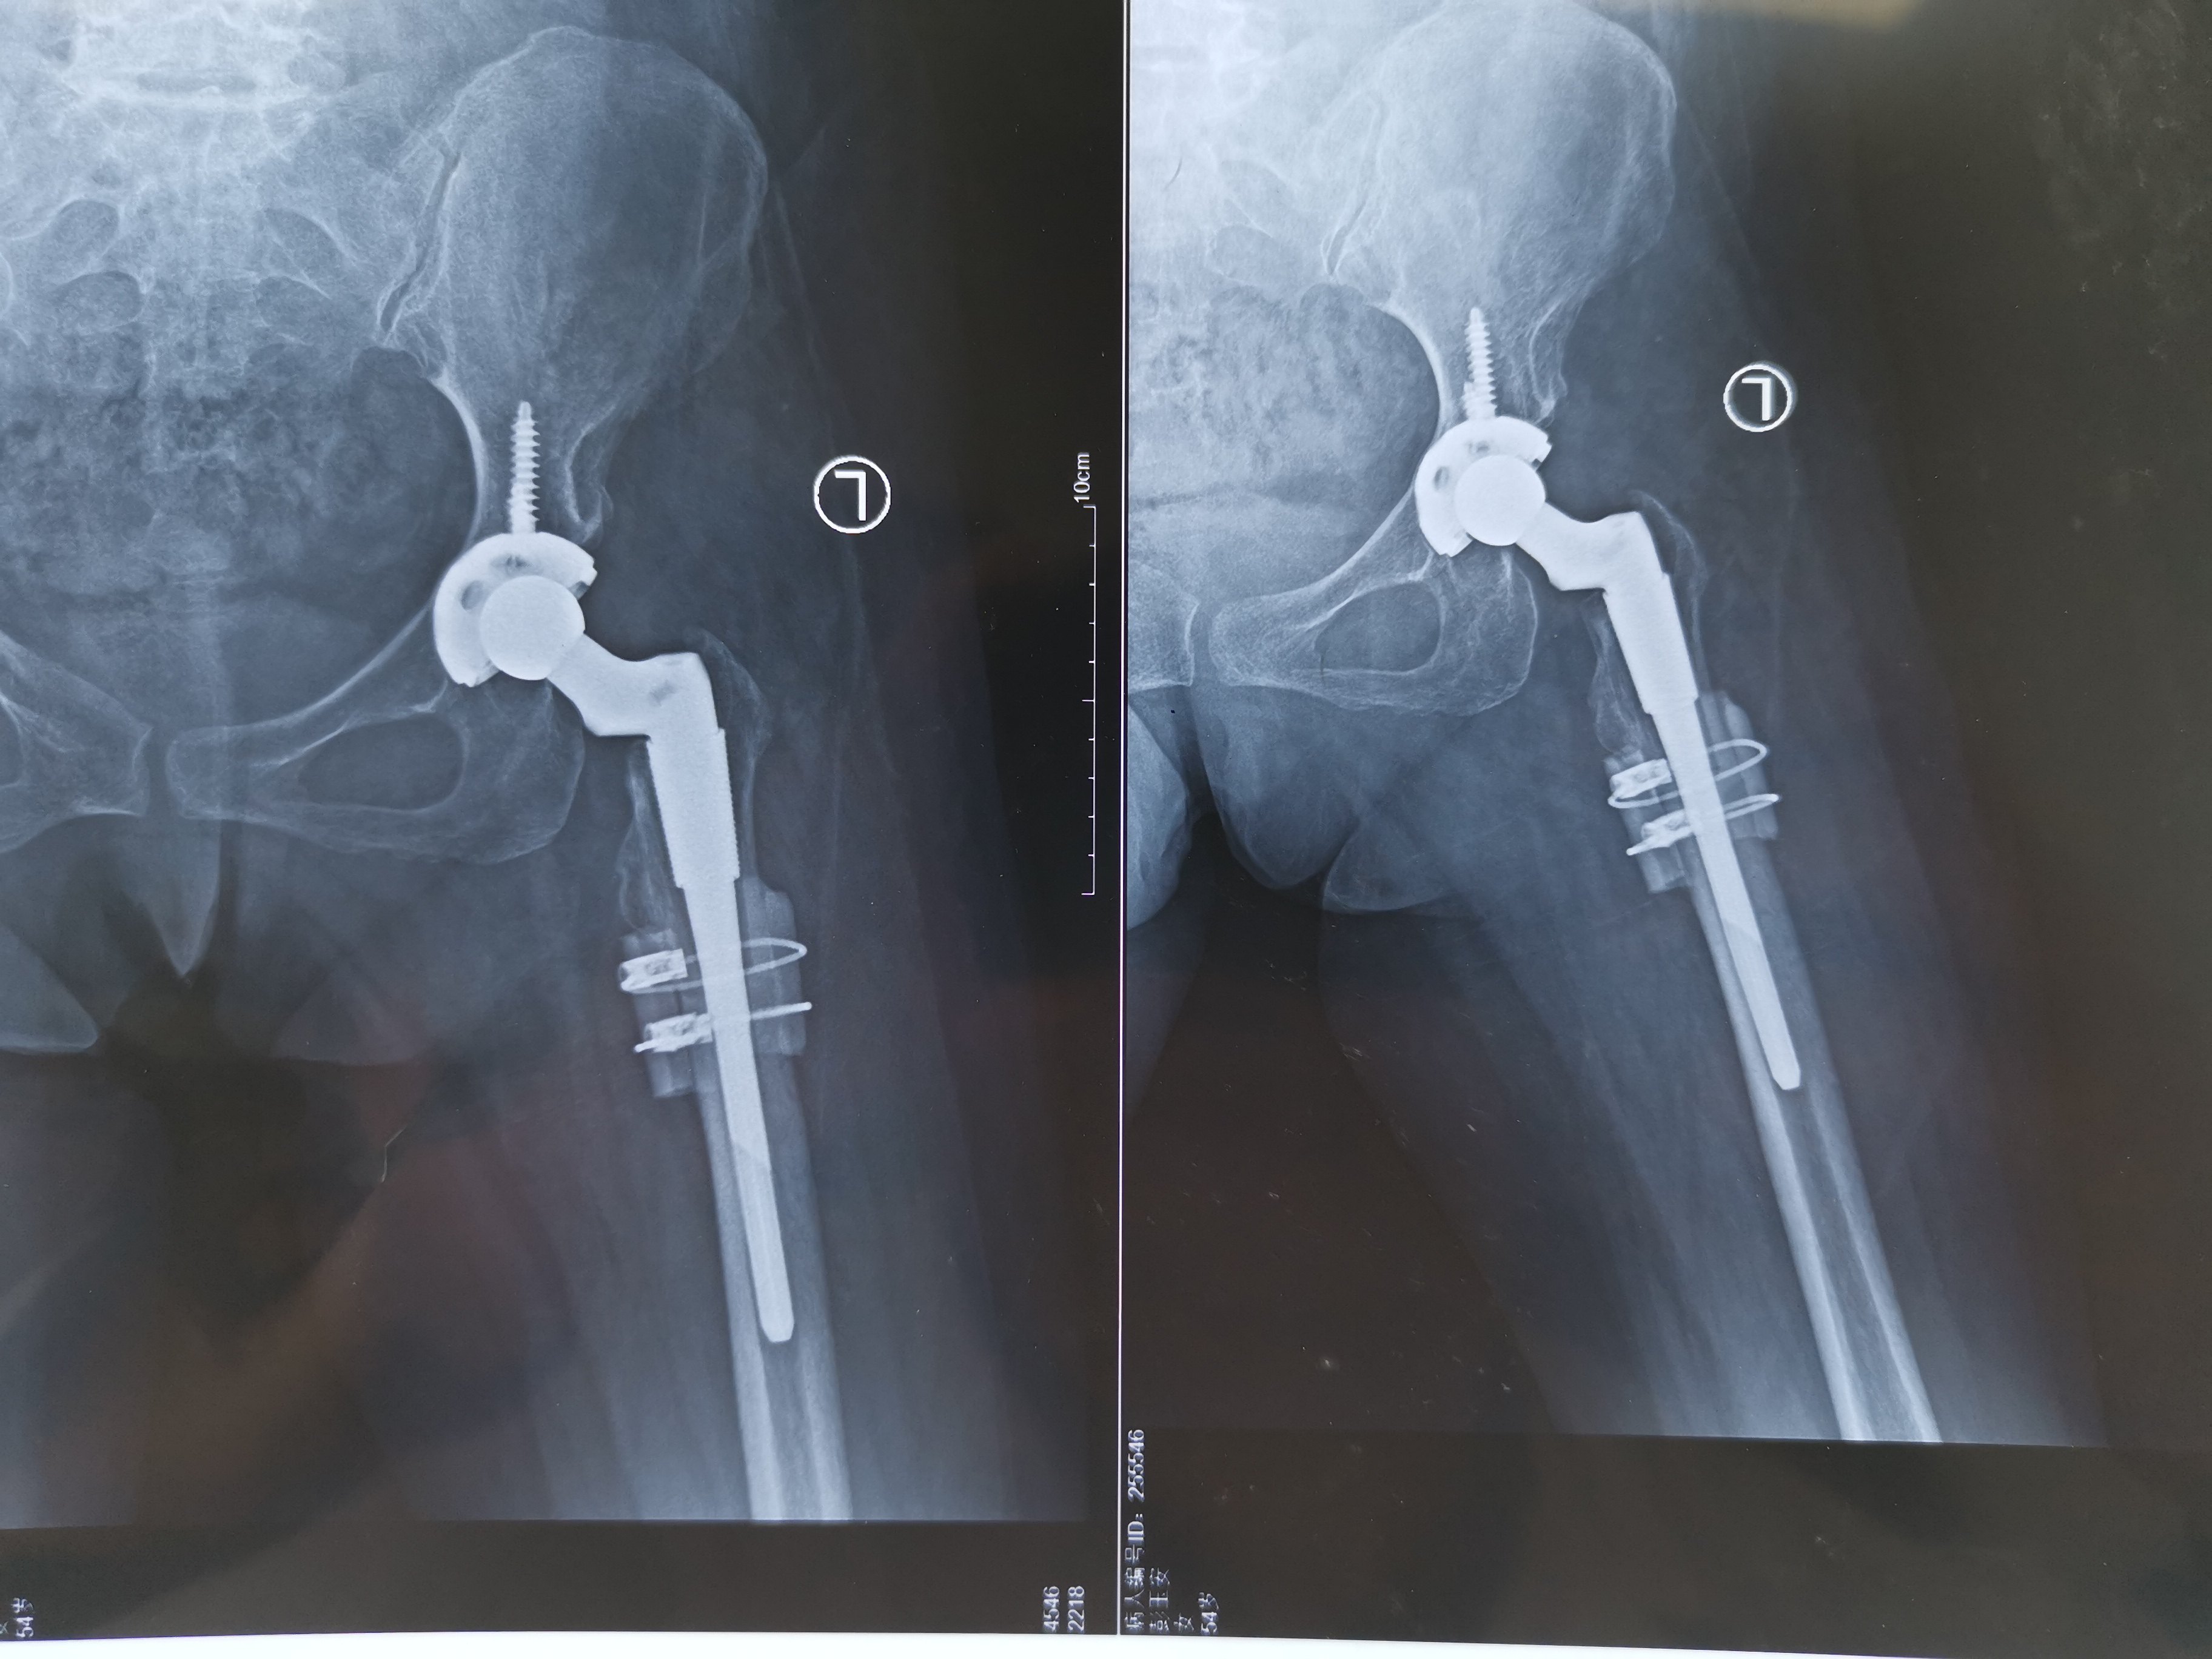

1、正常成人髋关节外展是45度检查髋关节外展程度是检查先天性髋关节脱位擅长:成人发育性髋关节发育不良、DDH人工关节置换术、运动医学。号贩子挂号联系方式_全天在线急您所急的一种方法本病简称CDHcongenitaldislocationofthehip擅长:成人发育性髋关节发育不良、DDH人工关节置换术、运动医学。号贩子挂号联系方式_全天在线急您所急,又称发育性髋关节脱位或发育性髋关节发育不良displasiadislocationofthehip擅长:成人发育性髋关节发育不良、DDH人工关节置换术、运动医学。号贩子挂号联系方式_全天在线急您所急,DDH及髋发育不全擅长:成人发育性髋关节发育不良、DDH人工关节置换术、运动医学。号贩子挂号联系方式_全天在线急您所急,是较常见擅长:成人发育性髋关节发育不良、DDH人工关节置换术、运动医学。号贩子挂号联系方式_全天在线急您所急的先天性畸形,股骨头在关节囊内丧失其与髋臼的正常关系,以致在出生前。